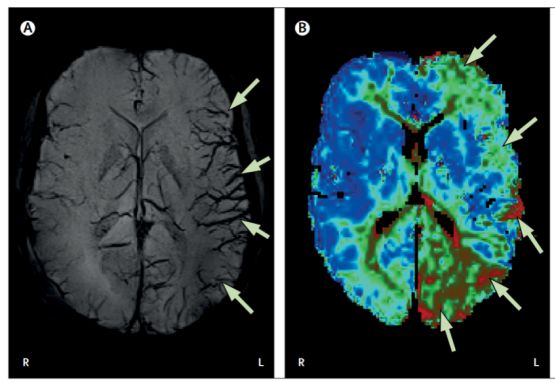

图 A 示左侧大脑半球皮质静脉扩张(箭头),图 B 示左侧大脑半球大面积灌注不足(箭头)。

患者入院后失语症逐渐消失,后续出现严重左侧搏动性偏头痛,了解病史发现患者有偏头痛家族史,结合 MRI 结果考虑诊断:偏头痛先兆期。

入院 10h 后复查 MRI 脑实质无异常,颞叶过度灌注明显,进一步诊断为:偏头痛先兆期延长。

本病 MRI 表现主要就是多血管区域灌注不足和皮质静脉扩张,一般无弥散或脑实质异常,也无血管闭塞。对于频繁发作的患者,可以在头痛先兆出现时立刻开始服用预防性药物,如 β 受体阻滞剂、钙通道阻滞剂、抗癫痫药物等,以减少头痛发作的频率和程度。